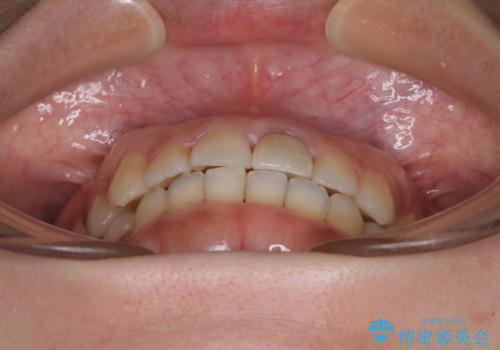

前歯のクロスバイトと変色した歯 ワイヤー矯正とセラミック治療

- 前歯のクロスバイトと神経を取り除いた後に変色してしまった前歯を気にして来院された患者様です。

ワイヤー矯正により矯正治療を行った後に、前歯の補綴治療を行うこととしました。

変色してしまった前歯は、反対側の歯と比べて歯肉が覆い被さっていたため、骨整形を含めた歯周外科処置を行い、歯肉ラインを整えることとしました。

歯周外科処置を行うかどうかは非常に悩んでいらっしゃいましたが、範囲がそれほど広くないため術後の痛みも強くないだろうということで、処置を行うこととなりました。